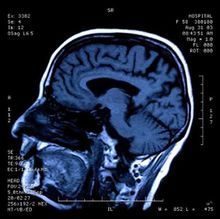

神經系統體檢有助於判斷小腦幕上病變,小腦幕下病變或代謝性疾病.周期性Cheyne-Stokes呼吸見於雙側大腦半球疾病或間腦病變,不規則的呼吸型式(延長的或共濟失調性吸氣)則見於橋腦下部或延髓上部的病變.過度換氣通常反映代謝性或肺部疾病,但有時候也反映橋腦上部或中腦的損害.在下丘腦疾病,橋腦疾病與麻醉品中毒時,瞳孔縮小但對光反射保存;當中腦受損,或發生嚴重過量的導眠能中毒時,瞳孔呈中等大小,反射消失.在缺氧或動眼神經受壓時,瞳孔擴大;在大多數代謝性疾病,半球疾病或心因性意識反應消失病例中,瞳孔反應都正常.在半球受到抑制的病例中,外耳道灌注冷水引起的前庭眼球反應顯示出可向雙側的強直性同向性偏斜,哪一側外耳道接受冷水灌注,雙眼球就向該側同向偏斜.腦幹受損時前庭眼球反應消失或出現非同向的眼球偏斜;在心因性反應喪失病例中只見輕微眼球震顫或隨機的不規則眼球活動.在半球病變中,偏癱的肢體對疼痛刺激不起運動反應.去大腦強直(頸項與背脊後仰,四肢伸直,牙關咬緊)見於間腦-中腦功能障礙;橋腦延髓腦幹障礙則引起四肢鬆弛性癱瘓.對稱的運動障礙,往往包括撲翼樣震顫或多灶性肌陣攣在內,見於代謝性疾病,特別是缺氧,以及藥物中毒引起的瀰漫性神經元異常,或Creutzfeldt-Jakob病.

在引起木僵或昏迷的小腦幕上病變中,神經體徵與症狀典型地首先提示一側大腦半球的損害.然後,由於占位性病變的擴大及顱壓增高引起腦組織移位,神經體徵反映壓迫作用自頭端向尾端擴展,首先累及間腦,最後累及腦幹.如果意識障礙是由原發的腦幹病變可引起,則一開始就可觀察到瞳孔與眼球運動的異常體徵.